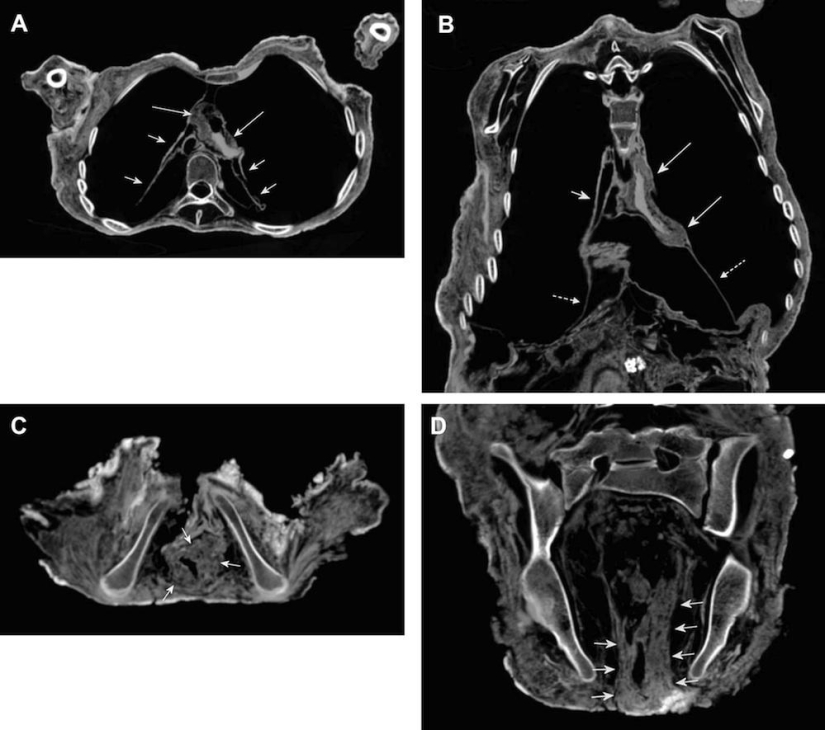

Las exploraciones también mostraron signos de una pared cardíaca compacta e intestinos hinchados. Lo más probable es que fuera causada por la enfermedad de Chagas.

Rayos X del cuerpo de la momia Inca.